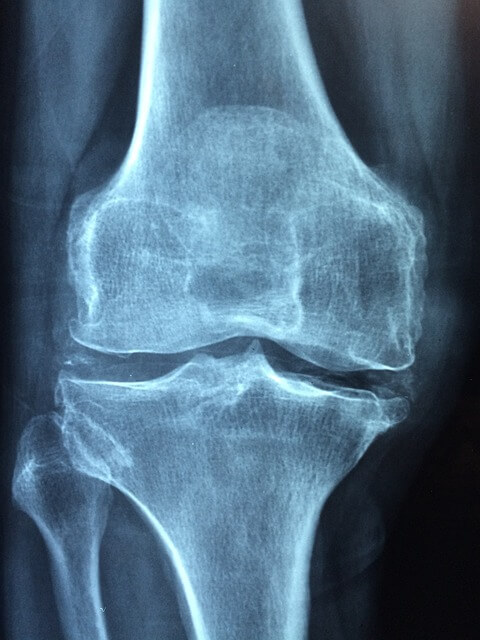

소연골유래 콘드로이친의 경우, 사람의 연골 분자 구조와 매우 유사하여 흡수가 빠른 것이 특징입니다. 도가니에는 콘드로이친과 콜라겐 성분이 풍부하게 함유되어 있어서 관절염 예방 및 완화에 효과적입니다.

예로부터 우리가 교통사고 등 관절부상을 입었을 때 소의 무릎뼈인 도가니탕을 푹 고아서 먹었던 것도 동일한 이유입니다. 단순한 민간요법이 아니었어요.

도가니를 오랫동안 끓이면 연골 속 콘드로이친이 우러나와 국물에 녹아들어 갑니다. 이때 함께 우러나는 콜라겐과 아미노산들이 시너지 효과를 만들어내죠.